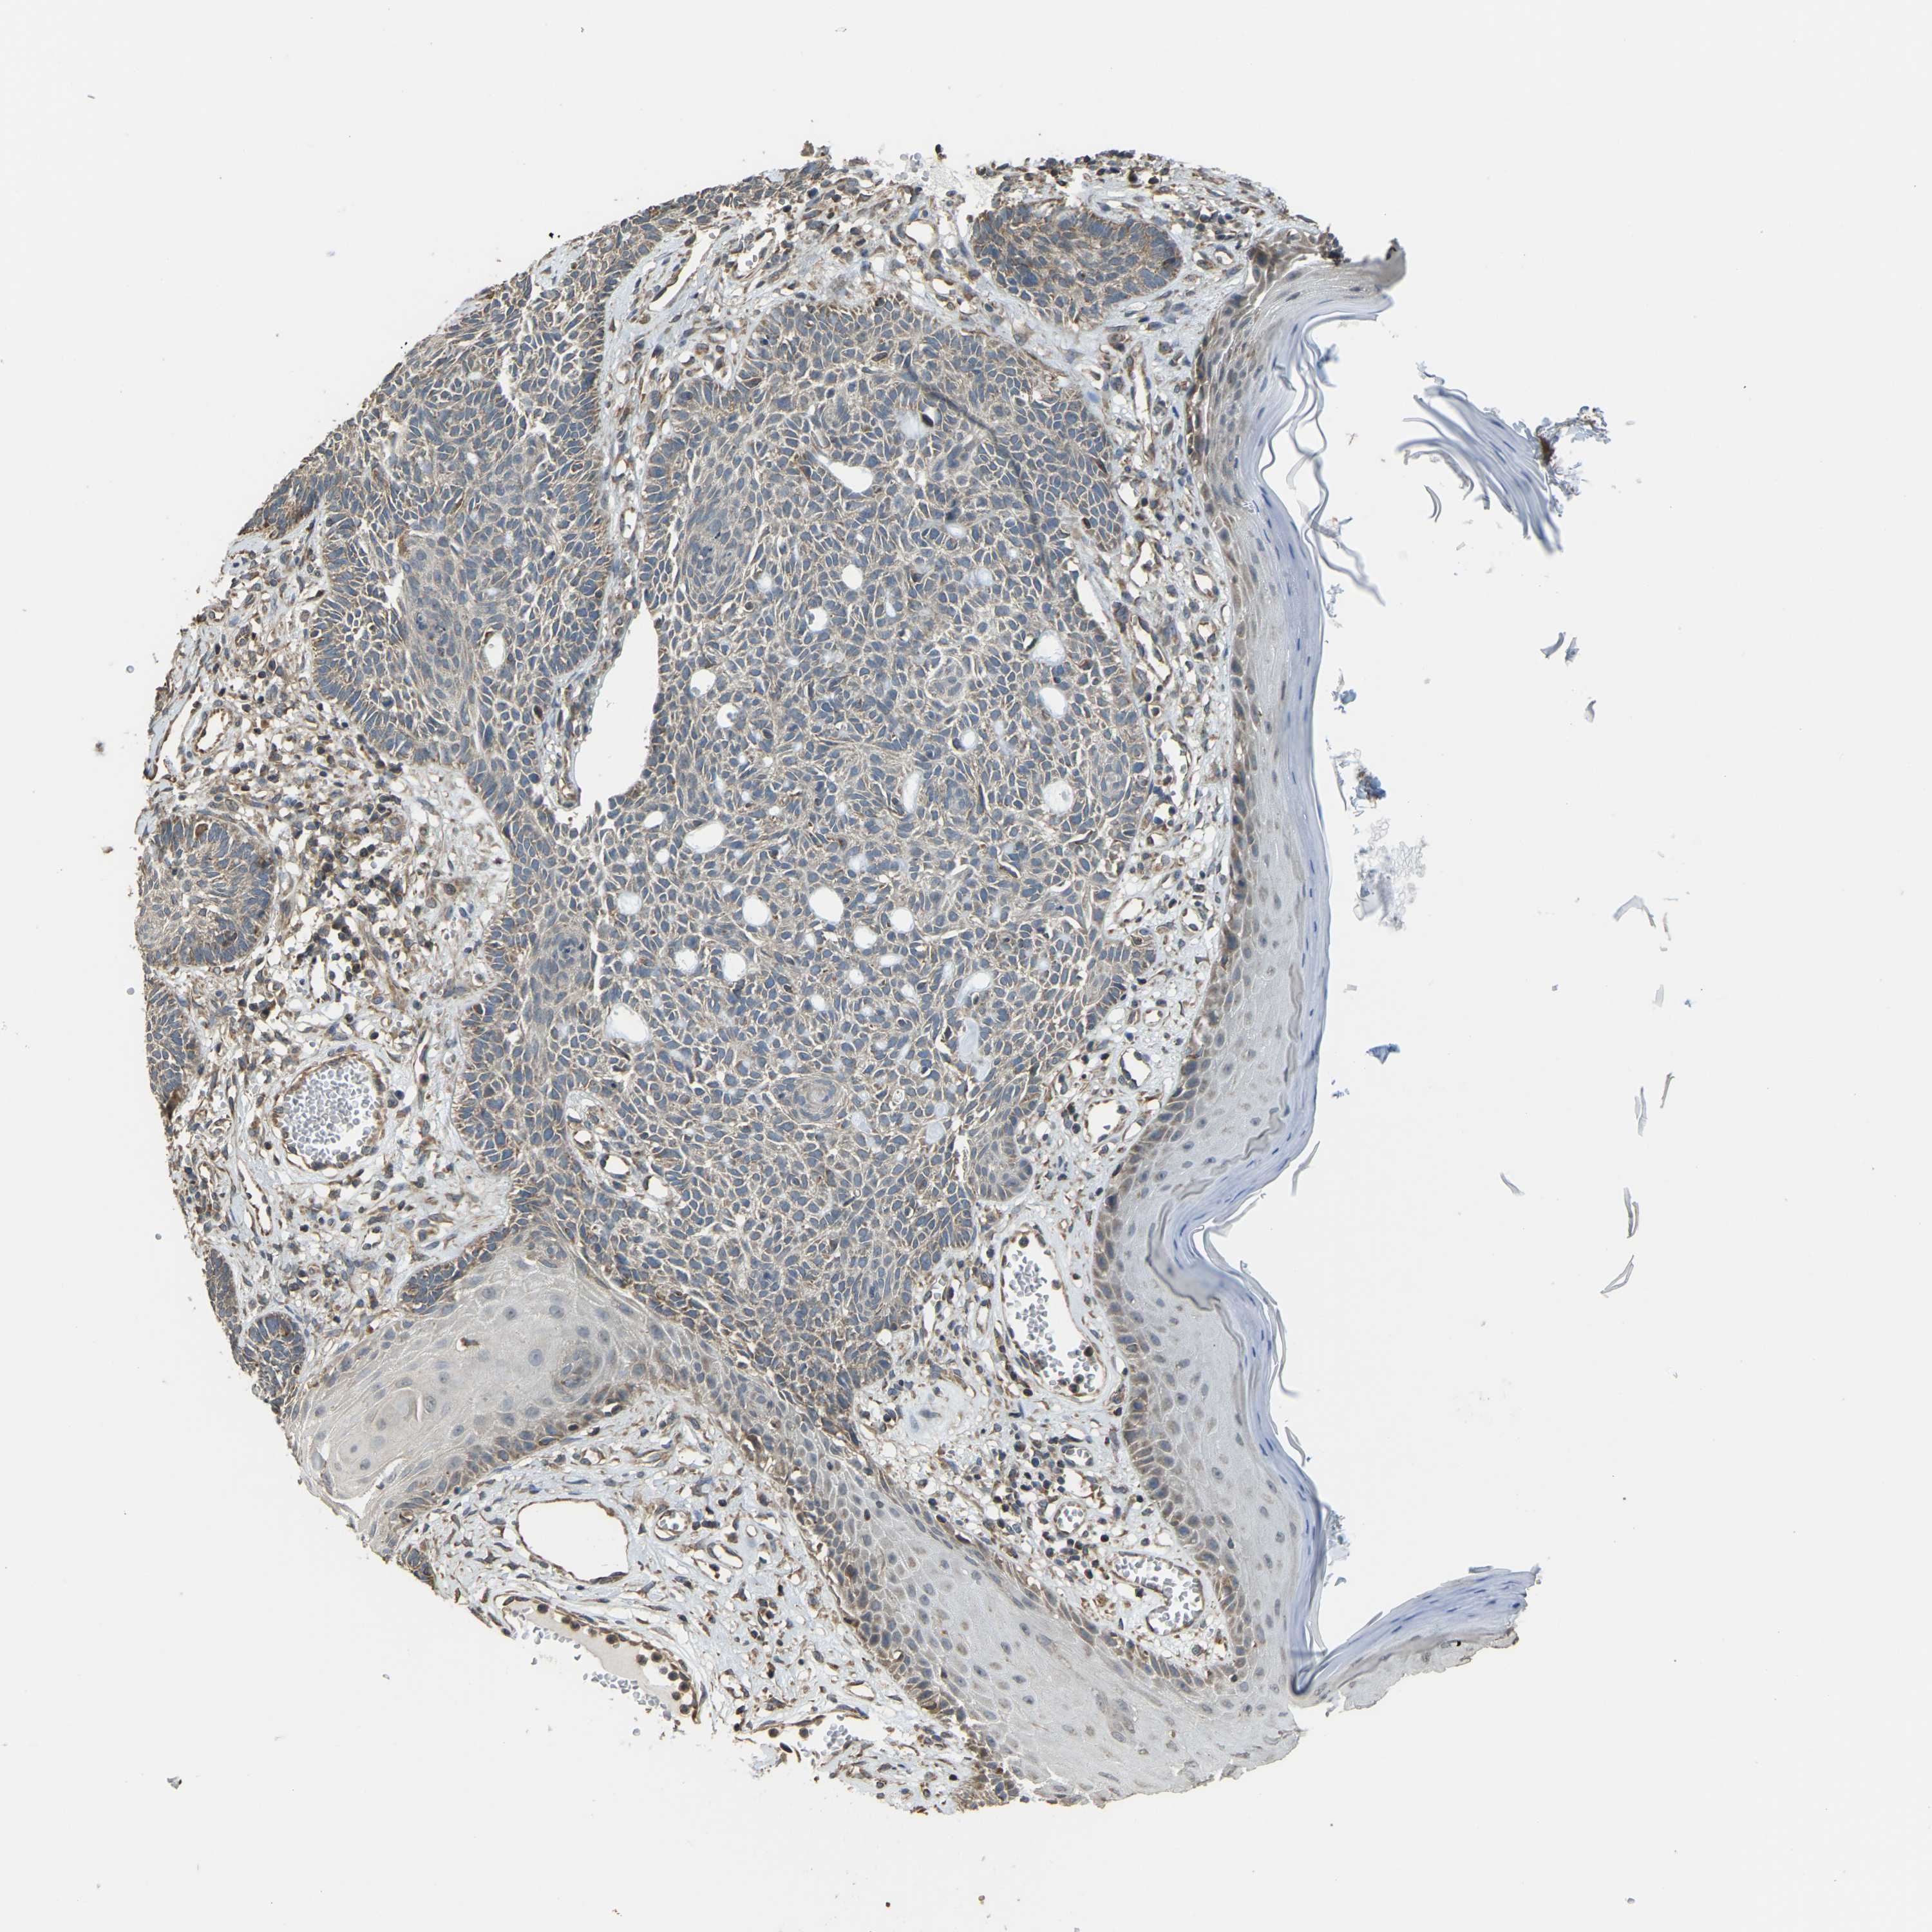

SKIN CANCER - Protein expressioni

A mouse-over function shows sample information and annotation data. Click on an image to view it in a full screen mode. Samples can be filtered based on level of antibody staining by selecting one or several of the following categories: high, medium, low and not detected. The assay and annotation is described here.

Each image is clickable and will lead to virtual microscopy that enables deeper exploration of all samples and also displays staining intensity scores, fraction scores and subcellular localization as well as patient and tissue information for each sample.

Antibody CAB018380

Staining

High

Medium

Low

Not detected

Intensity

Strong

Moderate

Weak

Negative

Quantity

>75%

75%-25%

<25%

None

Location

Nuclear

Cytoplasmic/membranous

Cytoplasmic/membranous,nuclear

Squamous cell carcinoma, NOS

Basal cell carcinoma

Squamous cell carcinoma in situ, NOS

Squamous cell carcinoma, metastatic, NOS

Adnexal tumor, benign